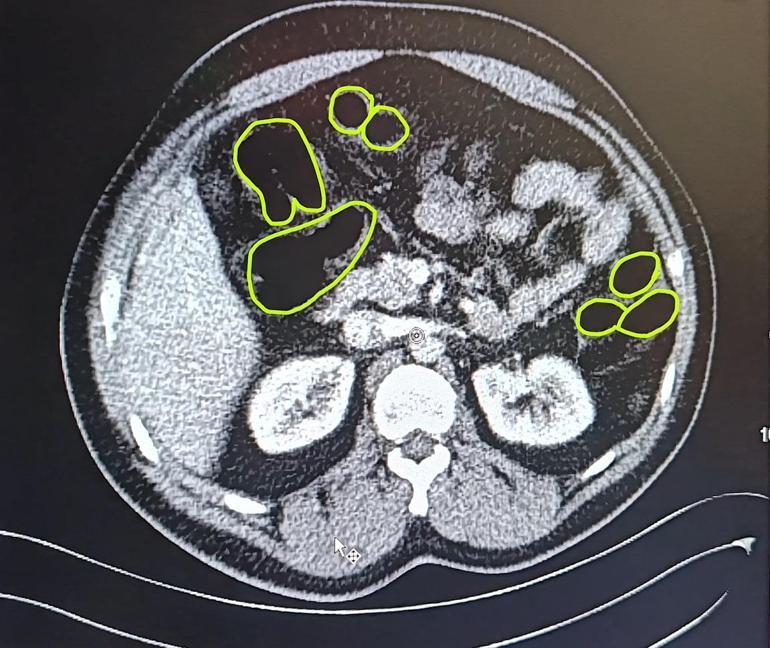

İl Jandarma Komutanlığı ekipleri, İran uyruklu A.O. (51), M.S. (37) ve P.S..'nin (28) ülkelerinden kente uyuşturucu getireceği bilgisine ulaştı. Şüpheliler Kocasinan ilçesi Himmetdede Mahallesi'nde taksi ile kente girmek istediği sırada durduruldu. Araçta yapılan aramada 15 gram esrar, 5 gram bonzai ve 117 adet uyuşturucu hap ele geçirildi. Gözaltına alınan 3 şüpheli muayene olmak üzere Kayseri Şehir Hastanesi'ne getirildi. Röntgen ve ultrason sonrası kontrollerde 3 şüphelinin midesinde uyuşturucu madde olduğu belirlendi. Şüphelilerin yuttukları uyuşturucuları kente sokmaya çalıştıkları tespit edildi. Kapsüller, sağlık ekibinin müdahalesiyle çıkarıldı. Taburcu edilen şüpheliler, İlçe Jandarma Komutanlığı'na götürüldü.